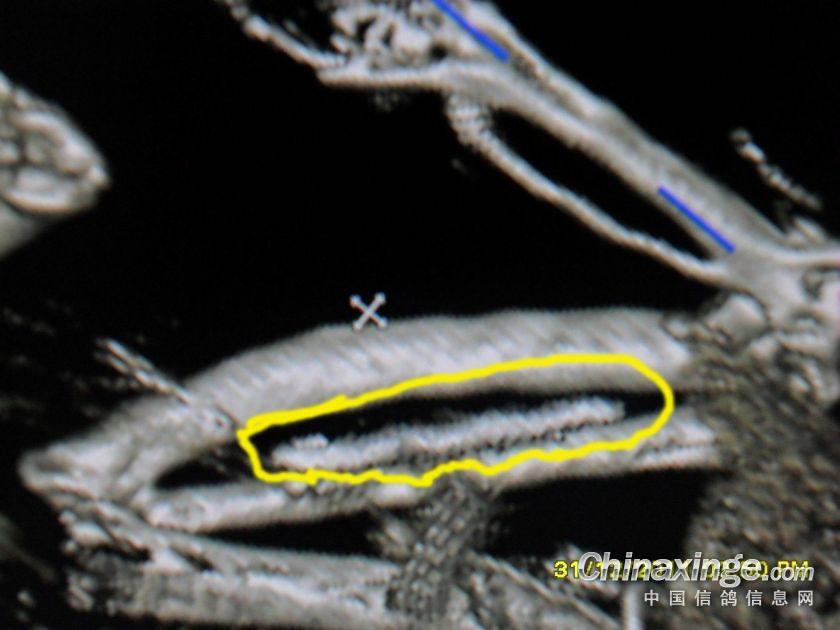

钢针插在翅膀内,翅膀肿胀,开笼后被迫落下!!!

金属物

在翅膀内的金属已经发炎

不同角度的金属物图片